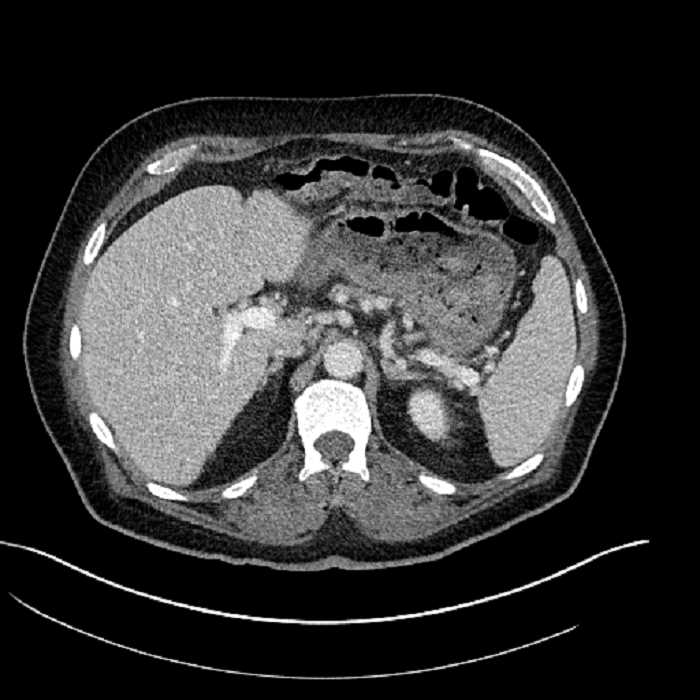

• Large fluid density structure in hepatic segments 7 and 8 measuring 10 x 7 x 7 cm with internal septation and circumferential ill-defined low density compatible with edema

• Peripherally enhancing subcapsular collections along the anterior margin of the left hepatic lobe measuring 3 x 1 cm and 2 x 1 cm

• Clearly marginated fluid density structure in segment 7 and several other scattered tiny hypodensities, which likely represent cysts

• Hepatic abscess

Acute sigmoid diverticulitis complicated by a small contained perforation and a large abscess in the right hepatic lobe. Additional small subcapsular abscesses along the anterior margin of the left hepatic lobe.

• The classic CT imaging appearance is a double target sign with internal low density surrounded by an internal enhancing rim (capsule) and a low density external rim (edema)

• Abscesses may be unilocular or multilocular

• Gas is present in a minority of cases

• Unfortunately, necrotic tumors can have an overlapping imaging appearance, so it is important to follow these to resolution

Hepatic abscess showing the double target sign with low density internally surrounded by a thin inner enhancing rim (red arrow) and ill-defined outer low density rim (yellow arrow). Blue arrow indicates an internal septation. Red arrows: additional smaller subcapsular abscesses. Red arrow: focal contained perforation associated with diverticulitis.